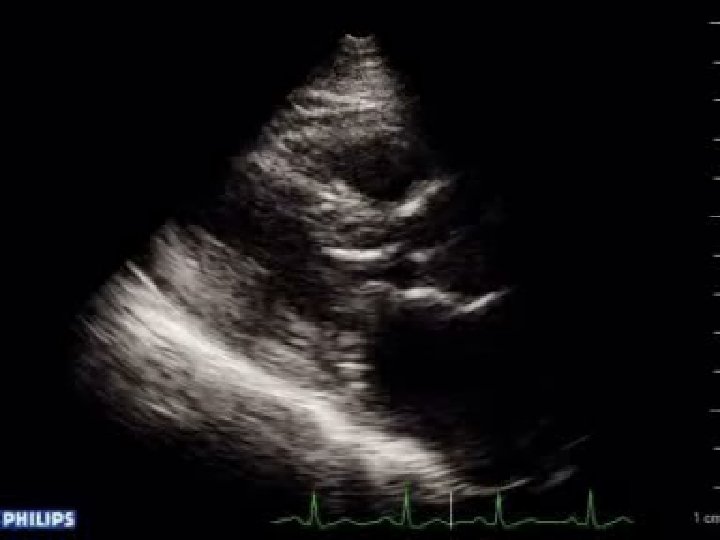

ESTENOSIS MITRAL ECOCARDIOGRAMA: Diametros de cavidades. Morfologia planos valvulares. FEVI. AVM. HAP. “Trombo” AI. Gradiente medio de presión: EM ligera= <7 mm. Hg EM moderada= 7 -14 mm. Hg EM severa= >15 mm. Hg

Graduación de severidad Normal : 6 cm 2. EM leve: cm 2. EM moderada: -1. 5 cm 2. EM severa: área entre 4 área entre 1. 5 -2 área entre 1 área < 1 cm 2.